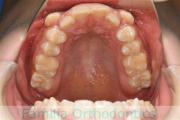

上顎

下顎